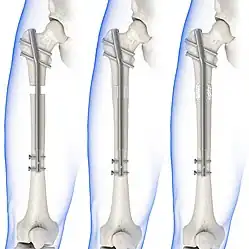

Treatment can be achieved by either non-operative (or conservative) or operative means. The main operative treatments for a Maisonneuve fracture are open-reduction surgery and closed-reduction surgery, both of which usually preceding internal fixation of the injury. These procedures are known as Open Reduction Internal Fixation (ORIF) and Closed Reduction Internal Fixation (CRIF).[6][13]

Internal fixators

Syndesmotic screws are the main, internal fixators used in surgeries for a Maisonneuve fracture. Two main types of syndesmotic screws are used: trans-syndesmotic screws (positioned at the level of the syndesmosis) and supra-syndesmotic screws (positioned above the syndesmosis).[14]

Based on several clinical results, syndesmotic screws are recommended to be fixed at least 1 centimetre proximal to the tibiofibular syndesmosis or 4 to 6 centimetres proximal to the tibiotalar joint line.[4][15] Cadaveric analyses, from a comparative study published in Foot & Ankle International in 1997, suggest that screw fixation at 2 centimetres proximal to the tibiotalar joint line is also adequate.[16] Biodegradable implants such as bioabsorbable screws, which do not require postoperative removal, may be used as an alternative to metallic hardware. However, biodegradable implants still limit rotation of the ankle and dorsiflexion of the foot.[4][6][13]

Following open-reduction, internal fixation is usually performed to stabilise the ankle mortise. To account for the distal fibula being slightly posterior to the distal tibia, drill holes are angled at 30° from the anteromedial aspect of the tibia to the posterolateral aspect of the fibula.[4][12][15] Trans-syndesmotic screws can be inserted in this way to ensure tibia fixation. Additional supra-syndesmotic screws may be temporarily inserted, for approximately 3 to 6 months, if instability is still present after fibular reduction. To reduce the fibula and restore the ankle mortise to its proper anatomical configuration, partial dorsiflexion of the foot is maintained prior to intraoperative screw fixation. This is because, in a neutral or maximally dorsiflexed position of the foot, the trochlear surface of the talus may reduce maximal postoperative dorsiflexion due to rigidity after screw fixation.[9][12]